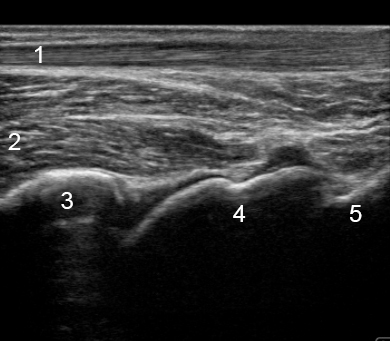

Image - Cheville : Vue postérieure longitudinale

1. Tendon calcanéen

2. Tendon du long fléchisseur de l'hallux (LFH)

3. Tibia

4. Talus

5. Calcanéus